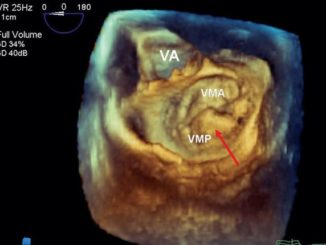

Prolapso de Valva mitral

O que é prolapso de valva mitral?

Prolapso da Válvula Mitral O Prolapso da Válvula Mitral (PVM), também conhecido como Síndrome de Barlow, é a anormalidade valvar [Clique e saiba mais]